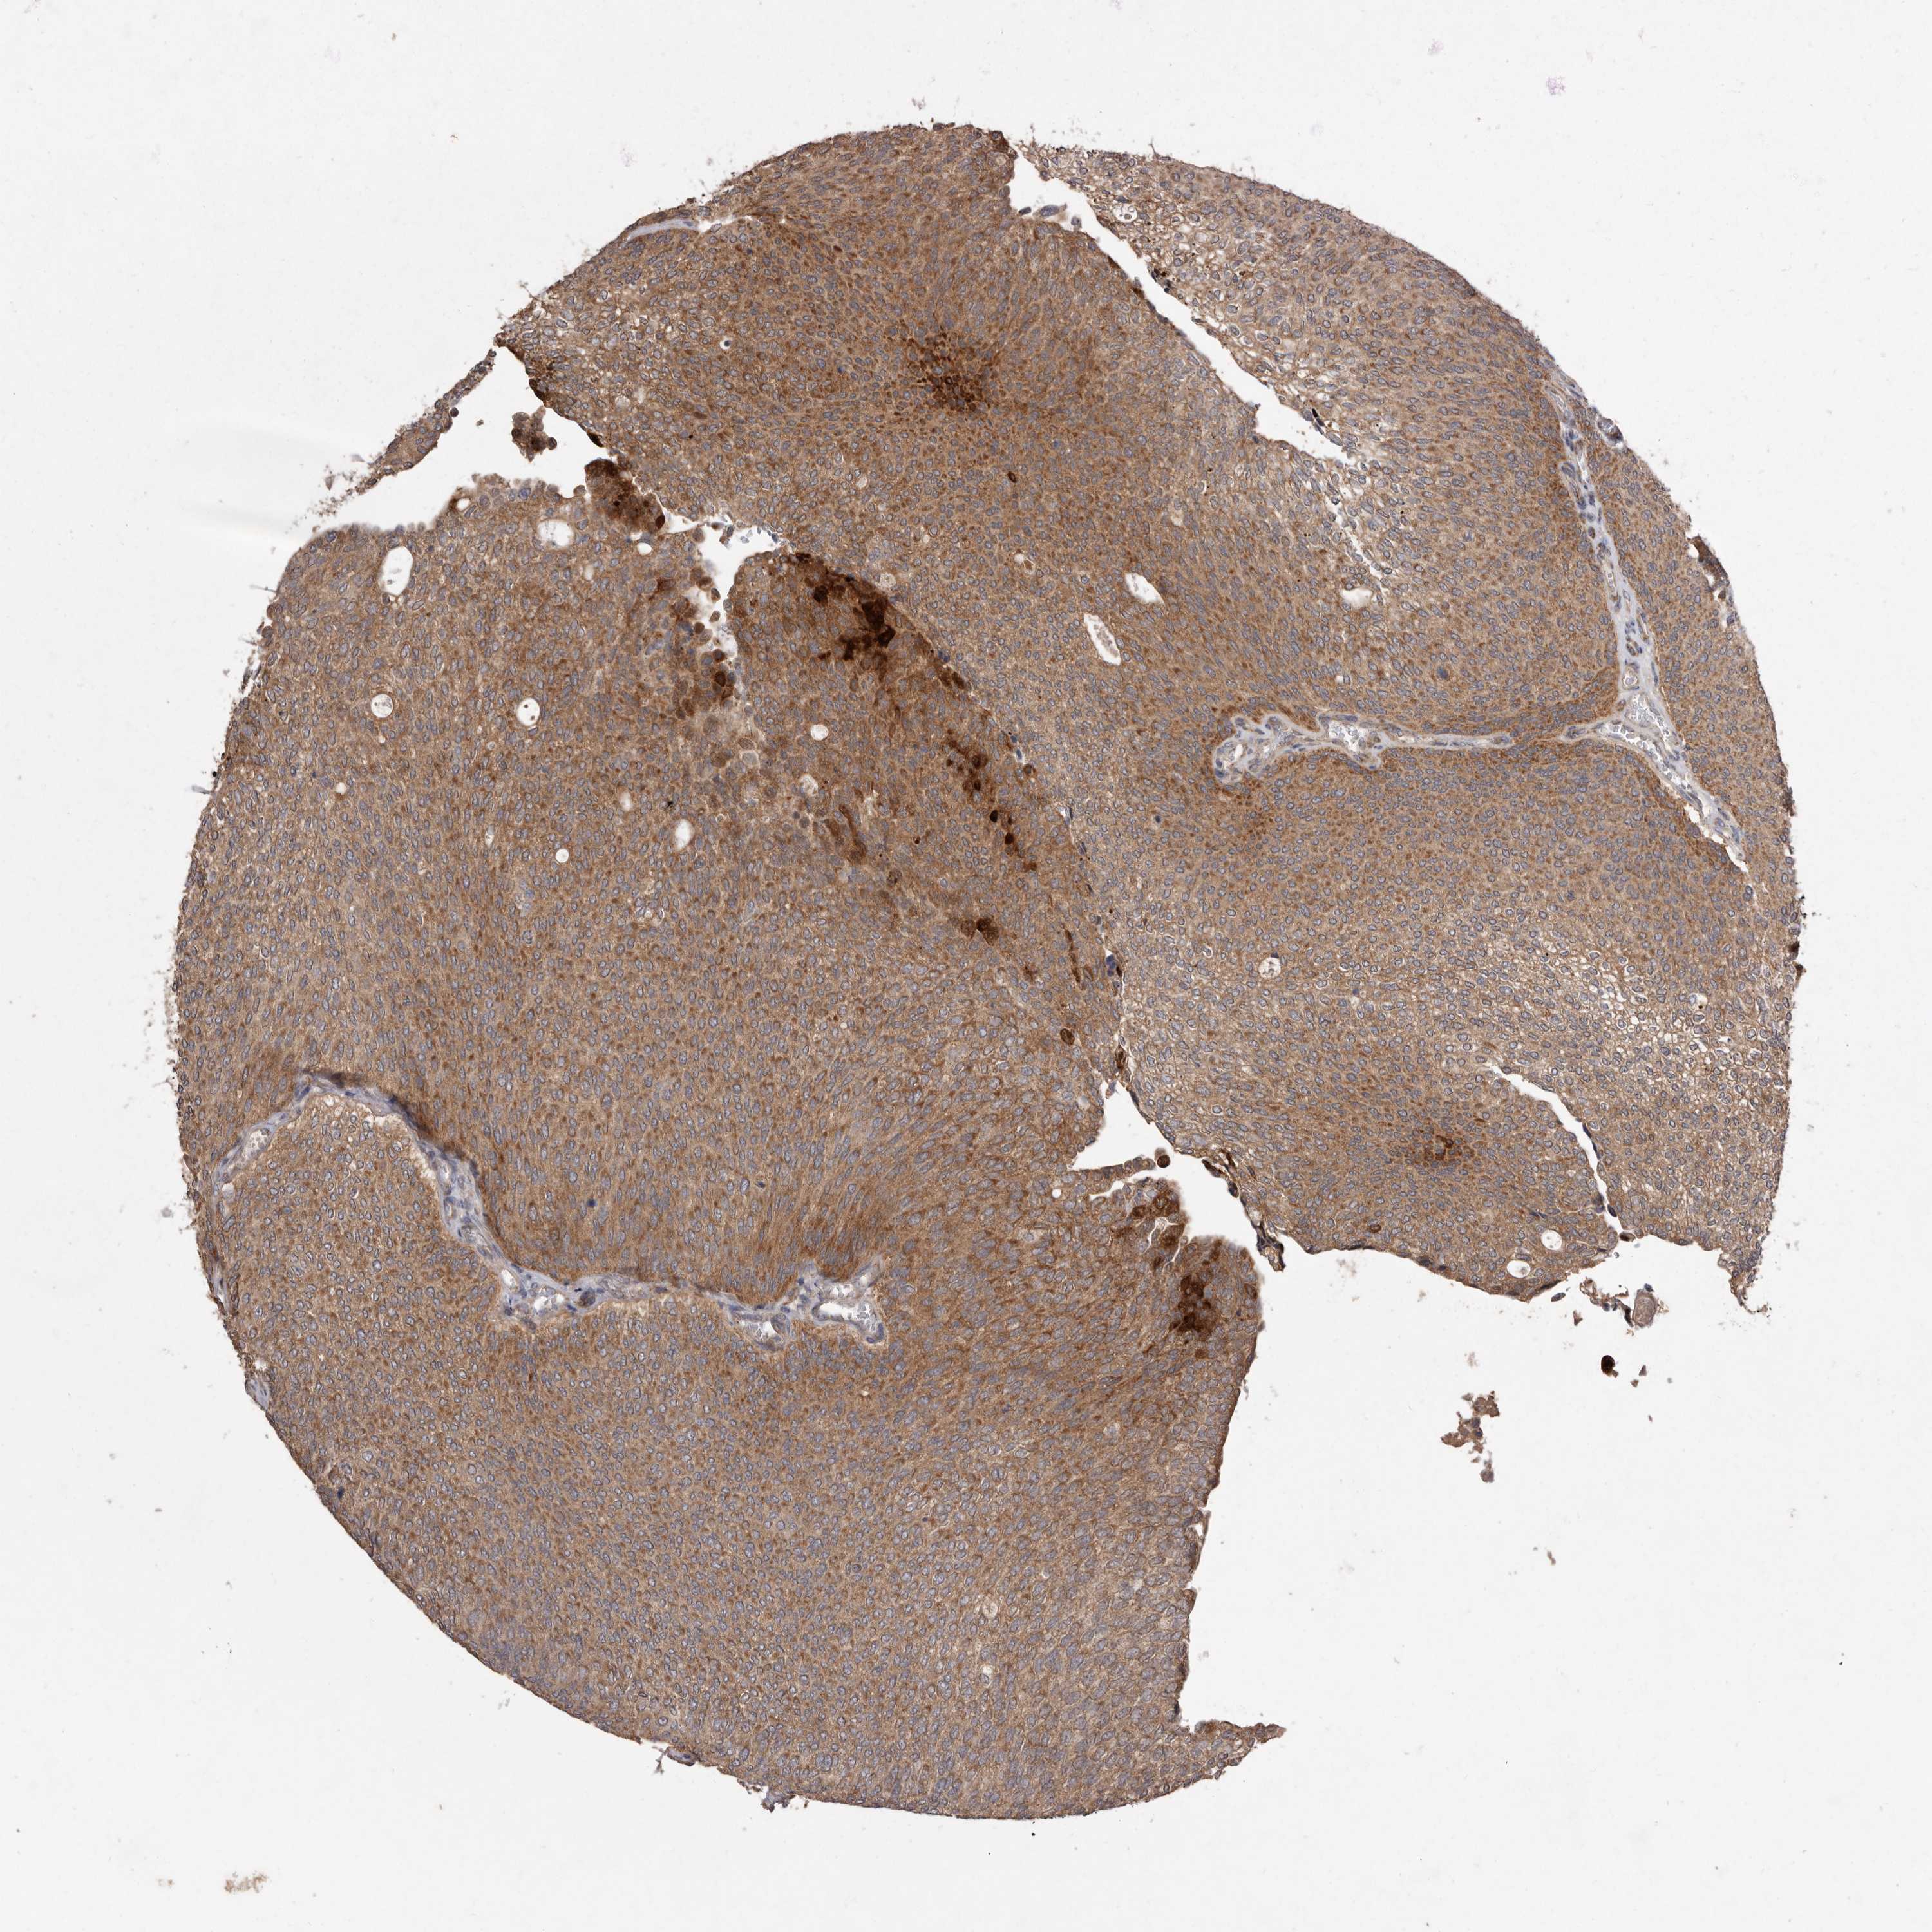

UROTHELIAL CANCER - Protein expressioni

A mouse-over function shows sample information and annotation data. Click on an image to view it in a full screen mode. Samples can be filtered based on level of antibody staining by selecting one or several of the following categories: high, medium, low and not detected. The assay and annotation is described here.

Note that samples used for immunohistochemistry by the Human Protein Atlas do not correspond to samples in the TCGA dataset.

Antibody stainingi

Antibody staining in the annotated cell types in the current human tissue is reported as not detected, low, medium, or high, based on conventional immunohistochemistry profiling in selected tissues. This score is based on the combination of the staining intensity and fraction of stained cells.

Each image is clickable and will lead to virtual microscopy that enables deeper exploration of all samples and also displays staining intensity scores, fraction scores and subcellular localization as well as patient and tissue information for each sample.

Antibody HPA028476

Antibody HPA028486

Antibody HPA028563

Urothelial carcinoma, Low grade

Urothelial carcinoma, High grade